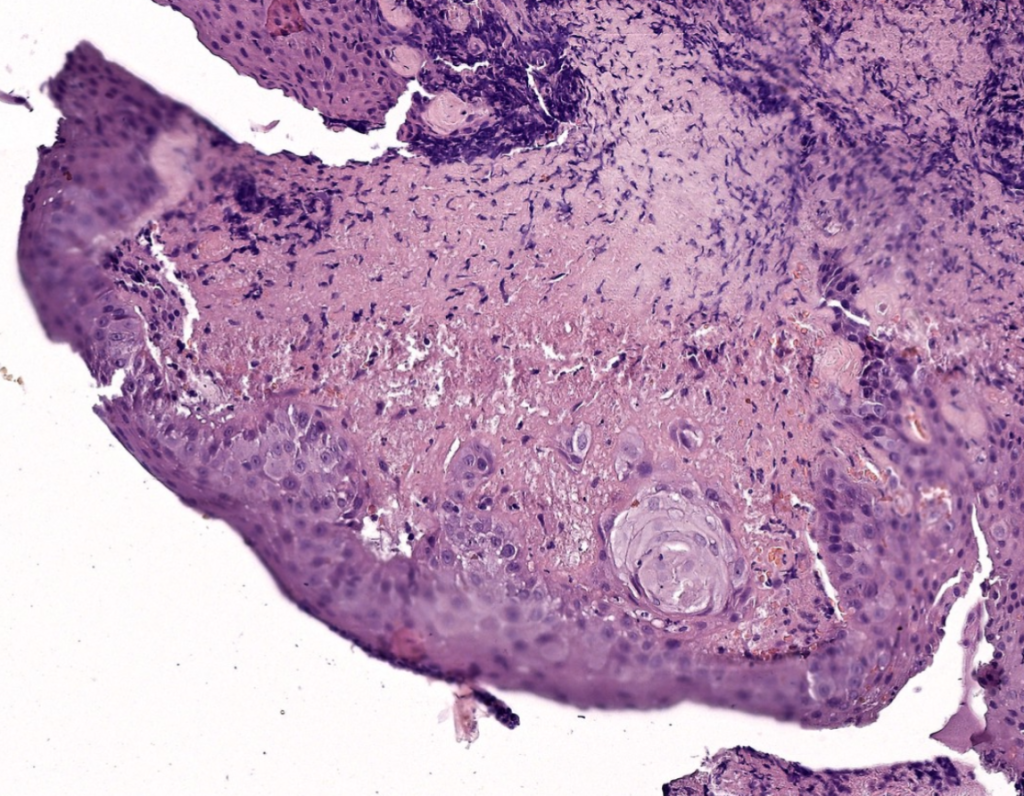

По результатам гистологического исследования образцов конъюнктивы было выявлено значительное расширение стромы за счет инфильтрации клетками воспаления, обнаружены крупные скопления макрофагов, которые располагались пластами и группами, были окружены коллагеновыми волокнами стромы и многочисленными разрозненными нейтрофильными лейкоцитами, плазматическими клетками. В образцах тканей из носовой полости отмечались выраженная пролиферация базальных слоев эпителия, плоскоклеточная метаплазия и дисплазия эпителия, строма также имела обширные участки накопления аморфного эозинофильного вещества (фото 4), окрашивание этого вещества PAS было положительным, Конго красным – отрицательным, что позволило исключить амилоидоз.

Гистологическое исследование ткани конъюнктивы при наличии в ней объемных образований – ценный метод диагностики, который позволил в данном случае поставить диагноз, поскольку обнаруженная субэпителиальная эозинофильная аморфная масса описывается во всех источниках литературы как характерная особенность при лигнеозном процессе2,5,10,11. Гистологическое исследование также позволило исключить иные объемные процессы конъюнктивы, например лимфому. Отбор материала конъюнктивы происходил на фоне уже начатого местного лечения глюкокортикостероидами и такролимусом, что могло влиять на информативность образца, но образцы поражений слизистой носовой полости были показательными, поэтому в случаях со сходной офтальмологической клинической картиной можно рекомендовать отбор ткани на исследование в кратчайшие сроки и без предварительной терапии. Большинство авторов считают клинические симптомы, результат гистологического исследования с обнаружением аморфной эозинофильной массы (конгорот-негативной) субэпителиально, гиперплазию и дисплазию эпителия достаточными основаниями для постановки диагноза.